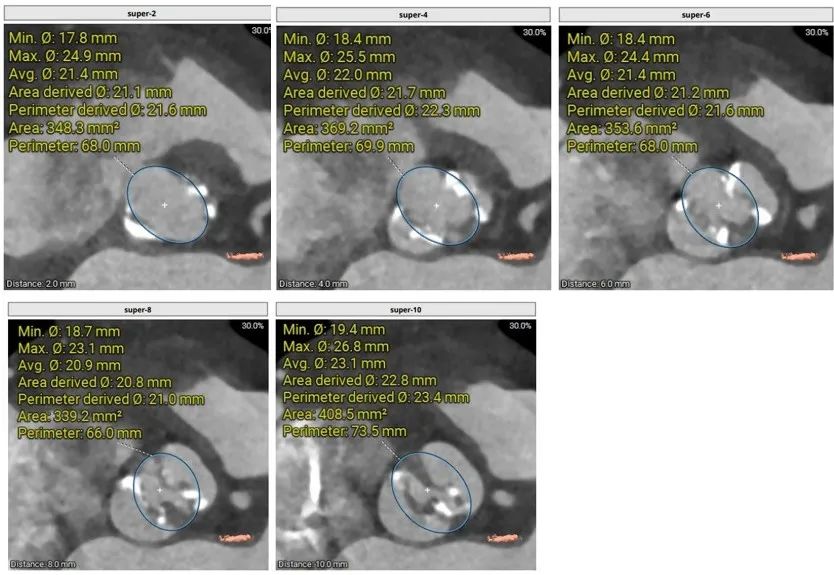

主动脉瓣根部:

Type0型二叶瓣环上结构:

瓣膜尺寸的选择:预装26,备选29: